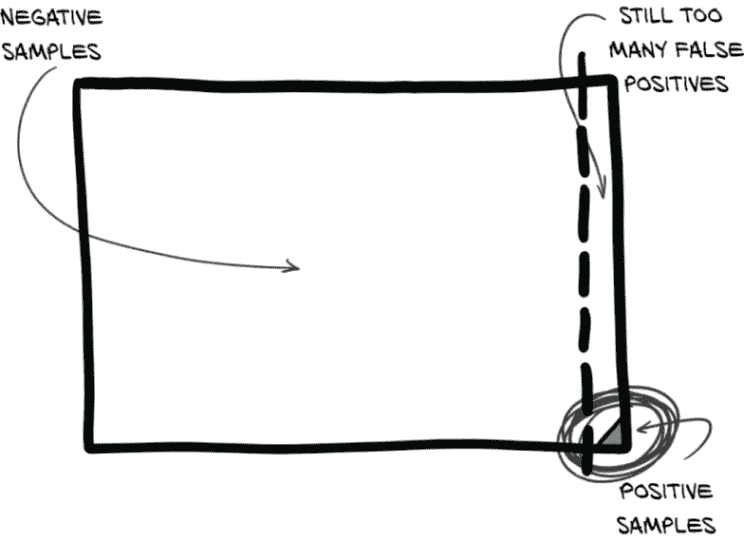

图 12.16 一个大致近似我们 LUNA 分类数据中不平衡的数据集

请记住,我们的数据极度不平衡。正样本与负样本的比例为 400:1。这是极端不平衡的!图 12.16 展示了这种情况。难怪我们的“实际结节”样本在人群中被忽略!

现在,让我们非常清楚:当我们完成时,我们的模型将能够很好地处理这种数据不平衡。我们甚至可以在不改变平衡的情况下训练模型到最后,假设我们愿意等待无数个纪元。但我们是忙碌的人,有很多事情要做,所以与其等到 GPU 烧毁到宇宙的热死亡,不如尝试通过改变我们训练的类平衡使我们的训练数据看起来更理想。